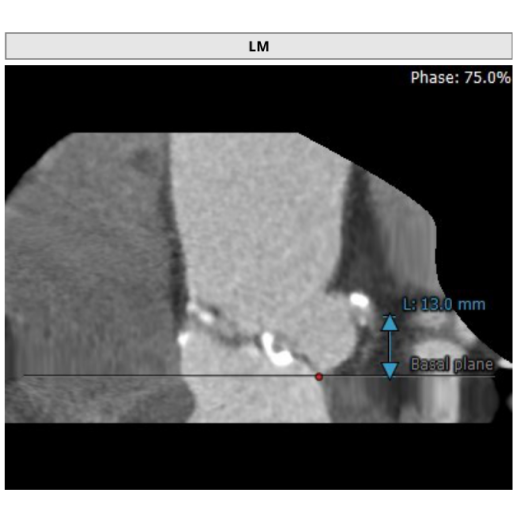

左冠高度:13.0mm,右冠高度:19.4mm